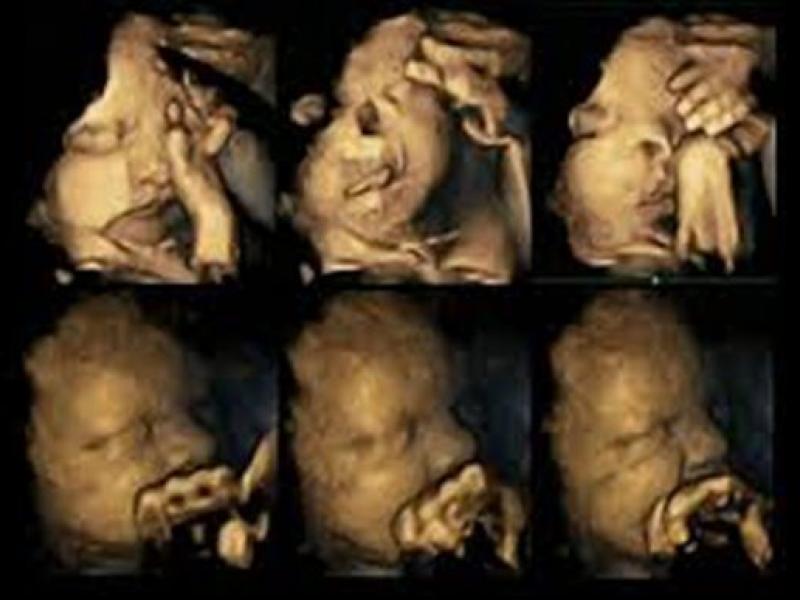

26.03.2015 - 06:18 Οταν η μητέρα καπνίζει «το έμβρυο μορφάζει από αγανάκτηση» Υπερηχογραφήματα δείχνουν την ενόχληση του εμβρύου στην... επαφή με το τσιγάρο ΕΠΙΣΤΗΜΗ Οταν η μητέρα καπνίζει «το έμβρυο μορφάζει από αγανάκτηση»